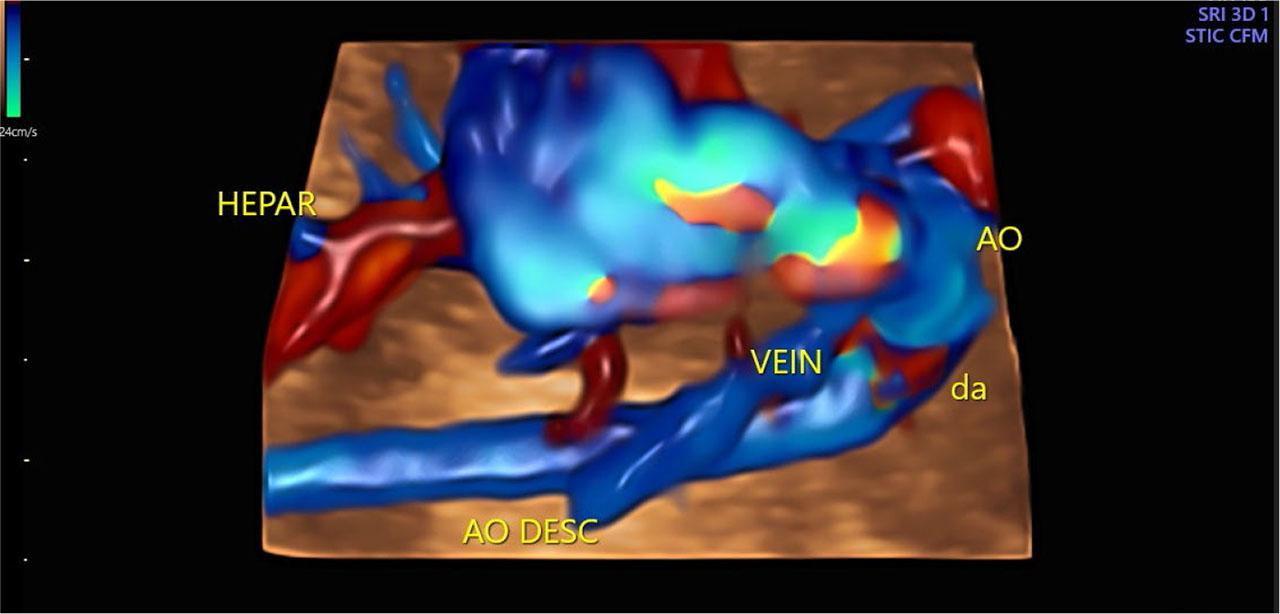

Fig. 3.